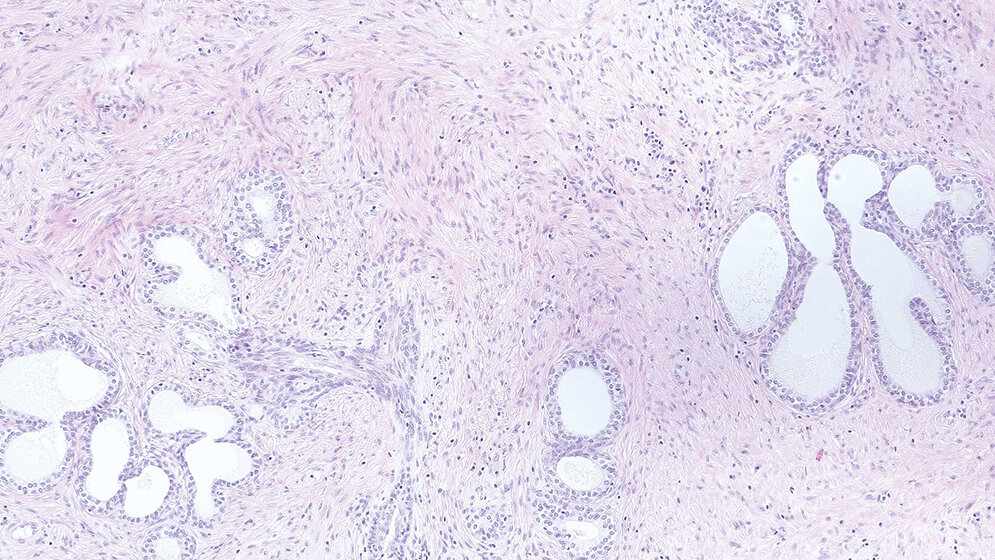

Die Prostata ist ein sehr kleines Organ, das den Männern im Alter allerdings große Probleme bereiten kann. Als Erkrankung ist eine gutartige Prostatavergrößerung im Alter sehr weit verbreitet, aber es gibt auch noch einige weitere benigne und maligne Erkrankungen, die in der Prostata auftreten können. Besonders bei den malignen Erkrankungen kann die Immunhistochemie (IHC) bei der Differenzialdiagnose sehr hilfreich sein.

The prostate is a small organ, but it can cause big problems for older men. A benign prostatic hyperplasia is common in old age. There are several other benign or malignant diseases that can occur in the prostate. Immunohistochemistry can be helpful in the differential diagnosis, particularly of malignant diseases.